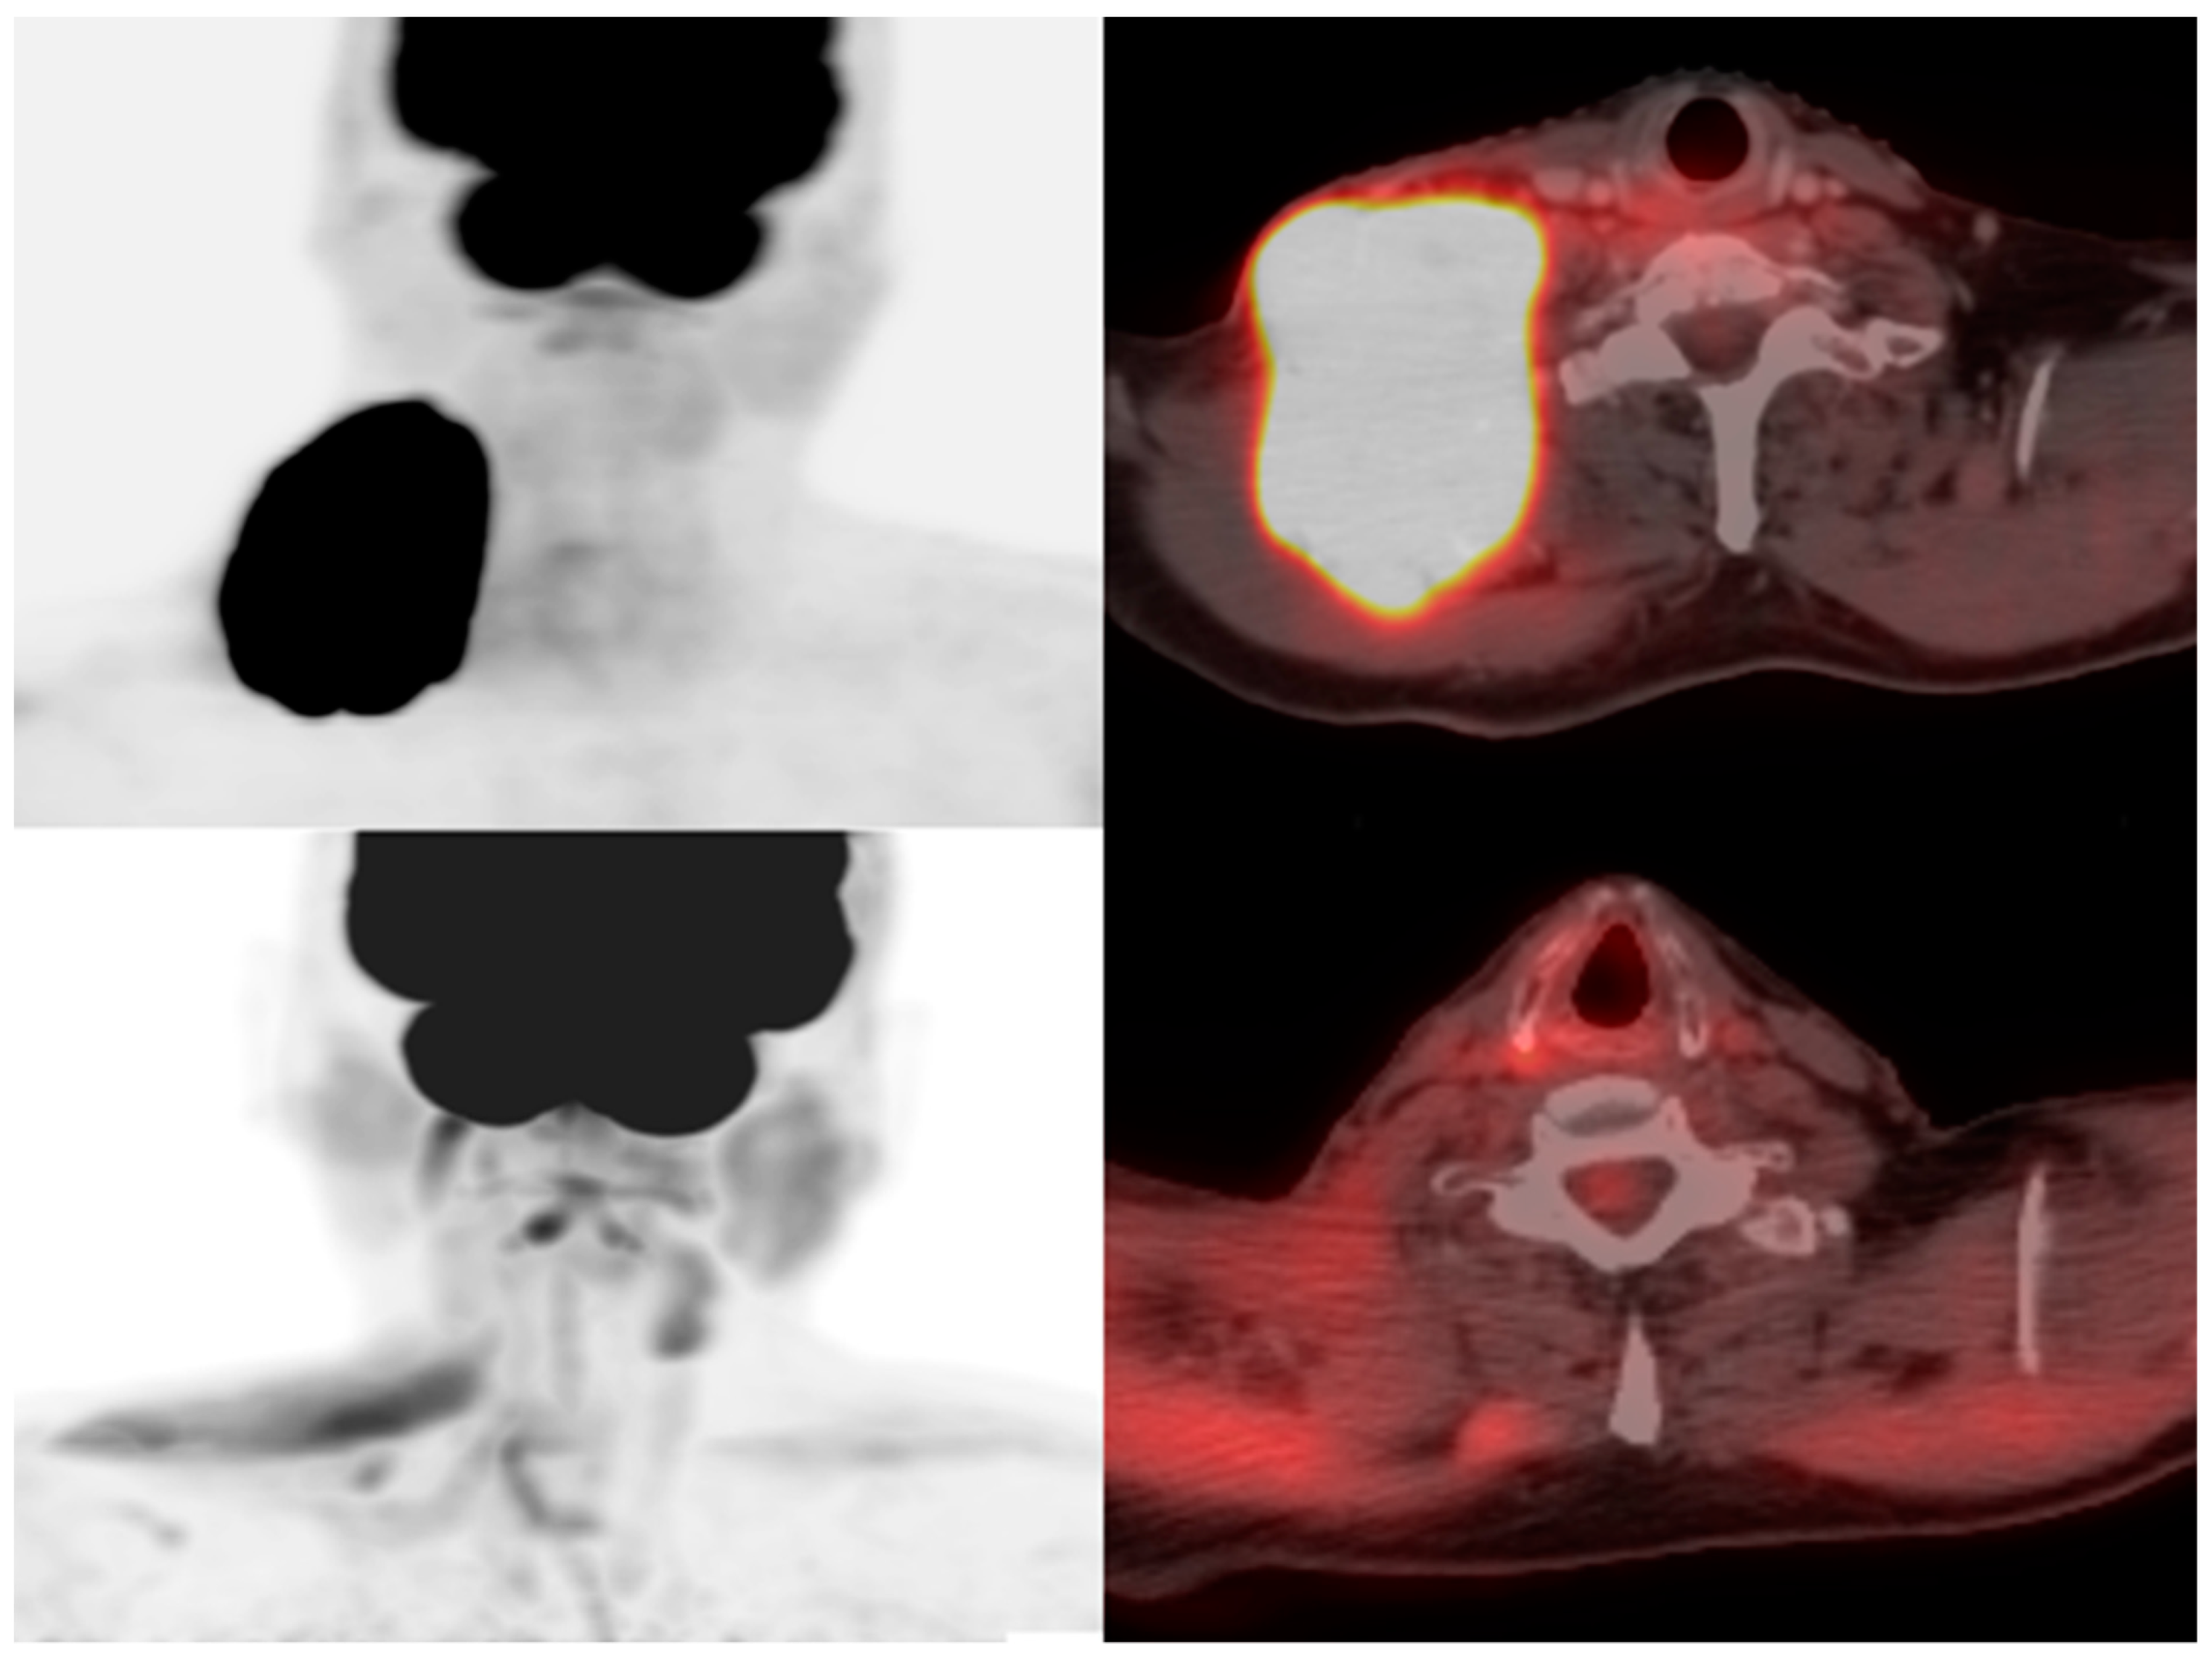

Figure 3.

A 73-year-old man with diffuse large B-cell lymphoma. Maximum intensity projection and axial fused FDG PET/CT pre- (above) and 28 days post- (below) CAR T-cell therapy demonstrating resolution of hypermetabolic adenopathy in the right lower neck consistent with complete metabolic response.